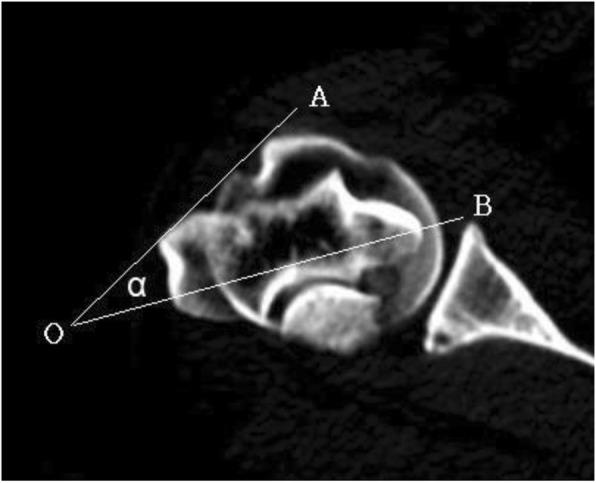

Twenty-eight normal humeral computed tomography scans were retrieved from our image database. One line was drawn through the vertices of the intertubercular sulcus of the humeral head in the coronal view, and another line was drawn through the longest axis between the medial and lateral condyles in the coronal view. The angle between these two lines was measured at least 3 times for each scan.

The profile of the intertubercular sulcus tangent line of the humeral head and the axis of the distal humerus was identified as the most accurate method for assessing the precision of torsion during MIS for humeral shaft fractures. The transepicondylar axis line is more internally rotated than the intertubercular sulcus tangent line. The mean angle was measured to be 41.1 degrees.

The axis of the distal humeral condyles is internally rotated by approximately 41.1 degrees compared with the intertubercular sulcus tangent line of the humeral head. Minimally invasive surgeries can be performed by using these palpable landmarks. The torsional deformities can be reduced with the proper angle adjustment without the need for fluoroscopy. It can also be used to treat unstable comminuted humeral fractures.